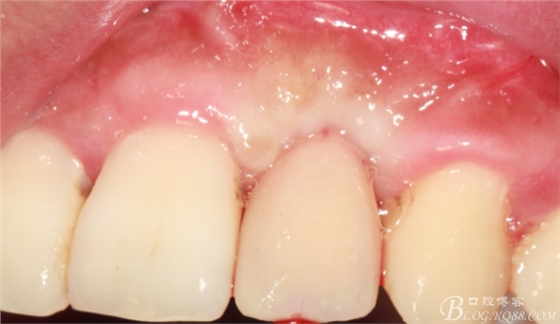

兩個(gè)月后戴入永久修復(fù)體。

戴入永久修復(fù)體當(dāng)天口內(nèi)照,雖有小瑕疵,但患者很滿意。

過程雖有曲折,時(shí)間有些長。但正是因?yàn)槲业膱?jiān)持不懈,正是因?yàn)槲业膱?zhí)著,最終取得相對滿意的結(jié)果?;颊呤翘欤颊呤巧系?,我不相信奇跡發(fā)生。認(rèn)真對待每一個(gè)患者,認(rèn)真對待每一個(gè)病例,遇到挫折不要等待奇跡發(fā)生,要積極主動(dòng)去應(yīng)對,去解決方是制勝法寶。希望通過這個(gè)病例能給各位老師提供一點(diǎn)點(diǎn)經(jīng)驗(yàn)。